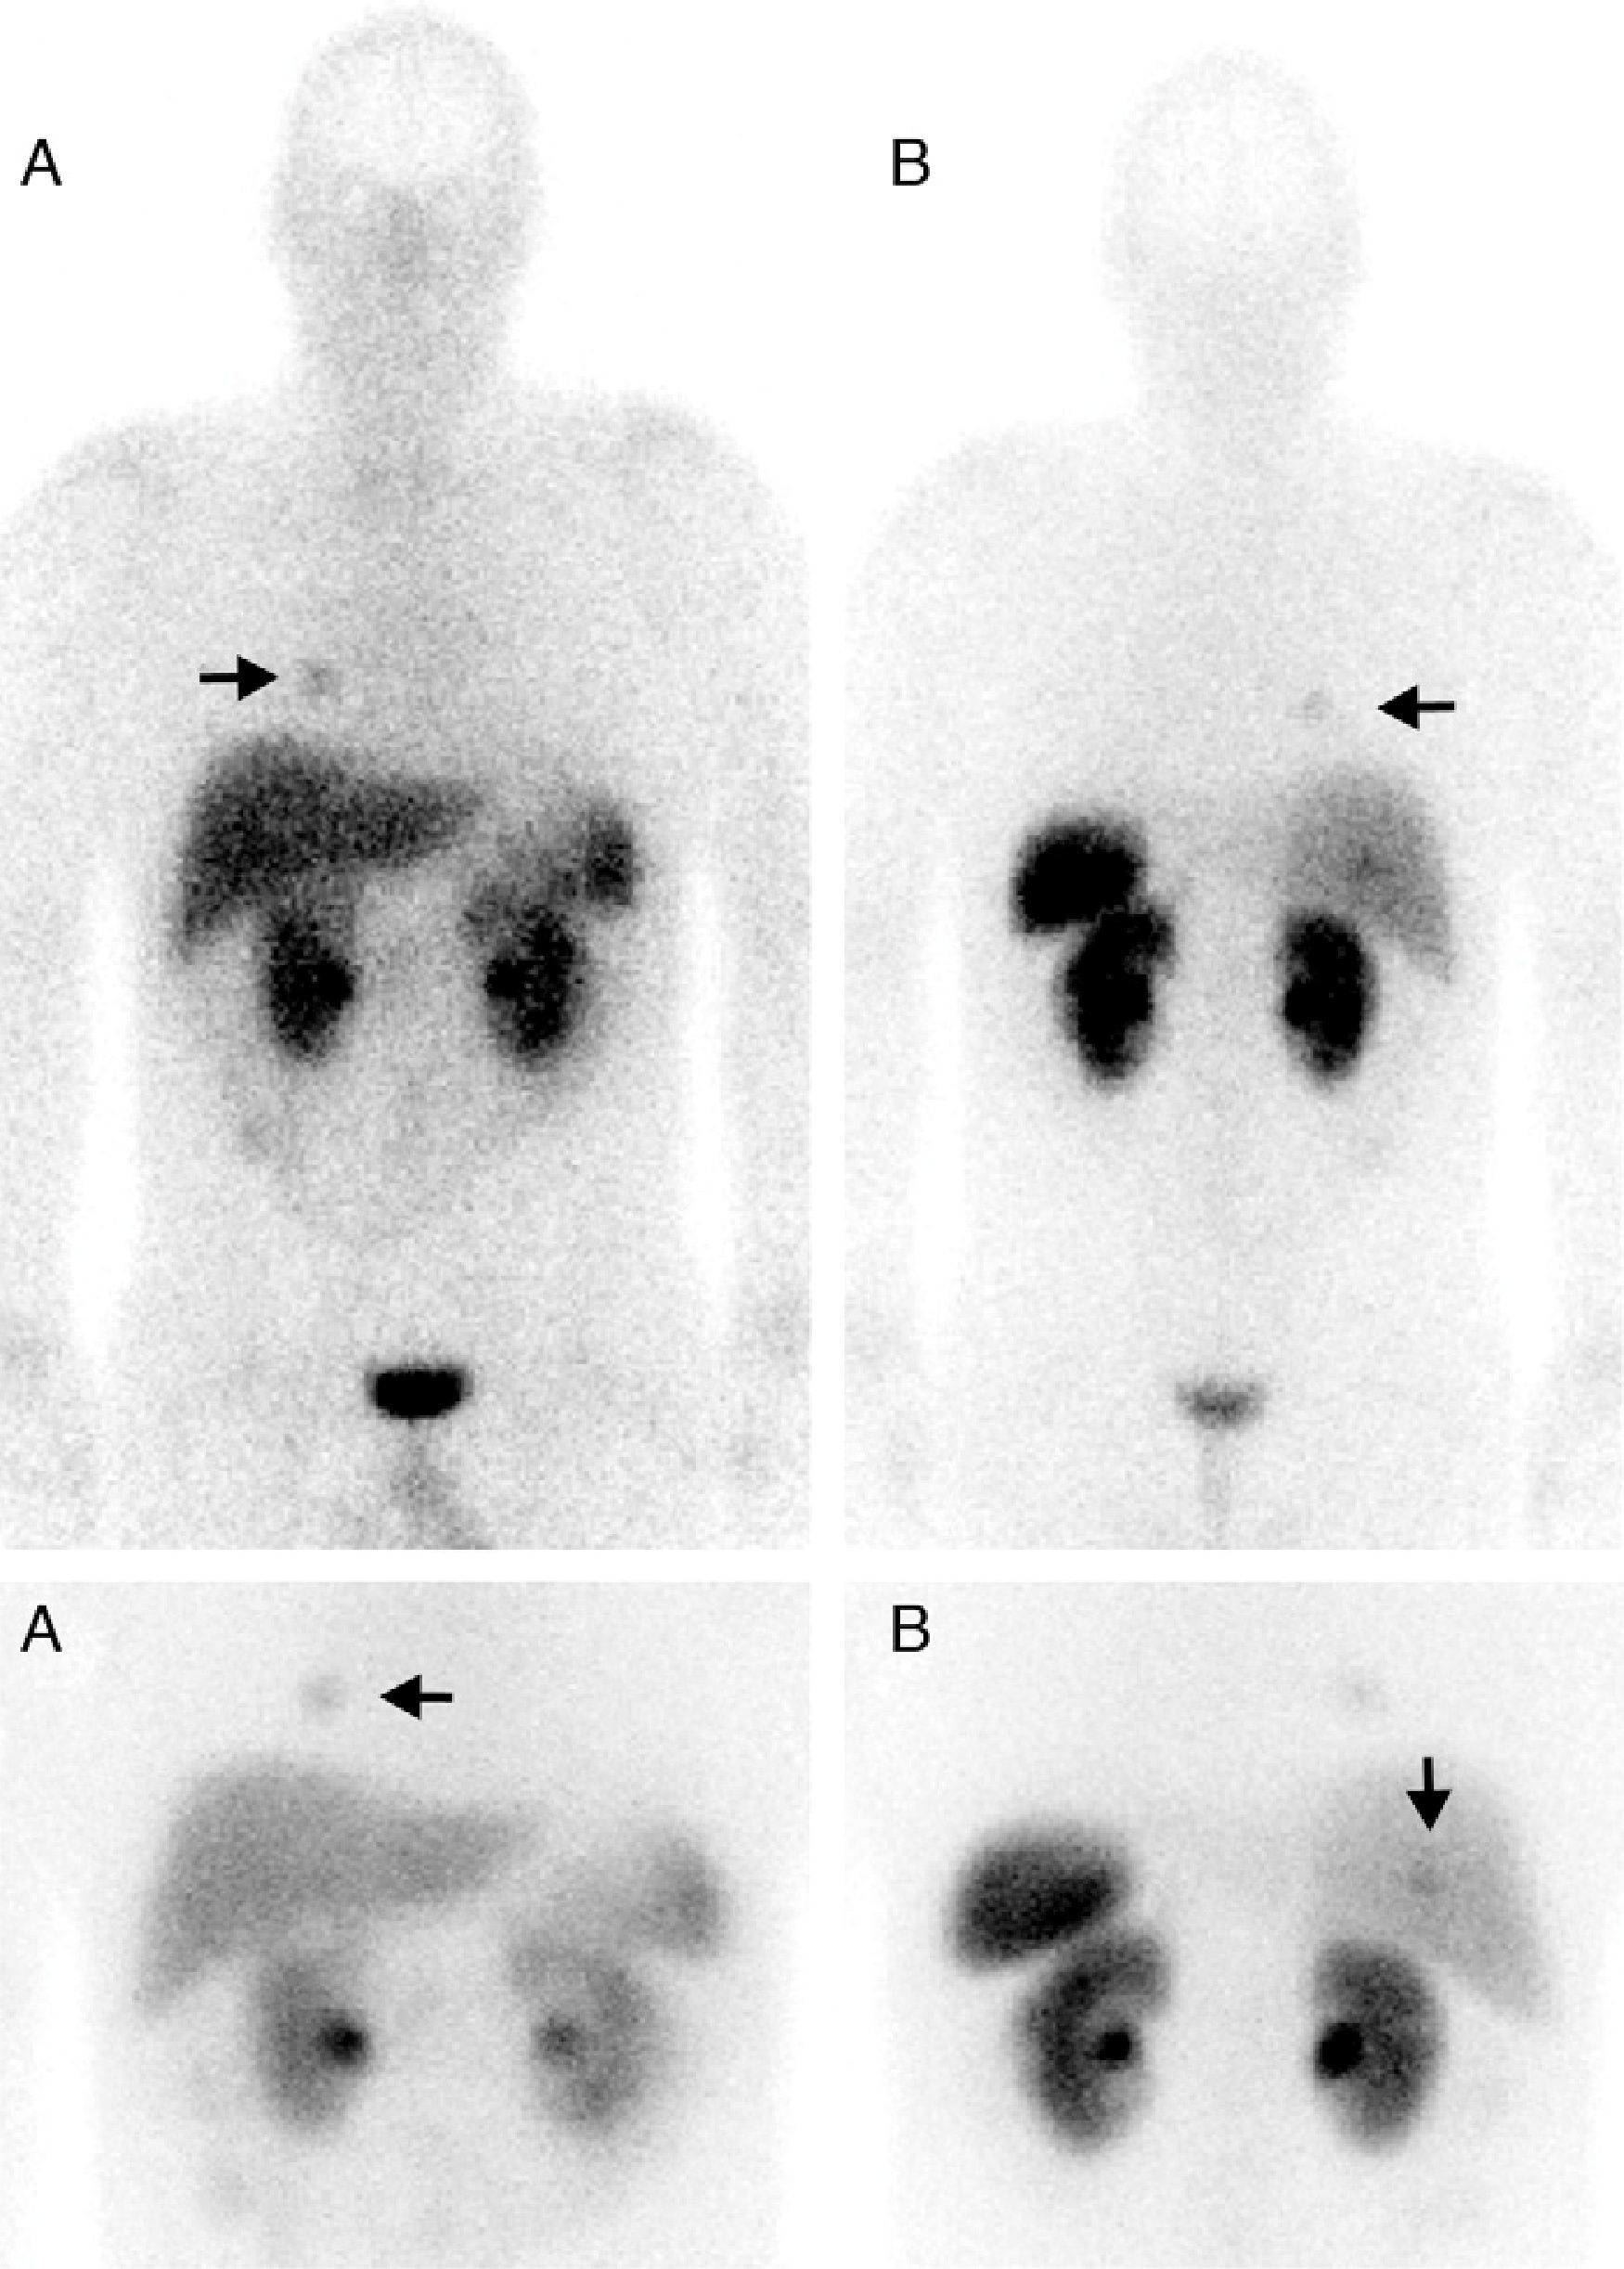

Multiple endocrine neoplasia type 1 syndrome (MEN1) is characterized by the presence of tumors in parathyroid glands, anterior pituitary gland, endocrine pancreas and duodenum. However, other tumors may also occur. One of them is the carcinoid tumor, which in this context, is more common in the gastrointestinal tract. Less common is the presence of carcinoid tumors of bronchial origin, which with histologic confirmation, may occur in 5–8% of cases and that appears more frequently in patients with hypergastrinemia.

We report a patient with MEN1 syndrome, hypergastrinemia and an incidental finding in a somatostatin receptor scintigraphy of an unsuspected bronchial carcinoid tumor that was confirmed histologically.